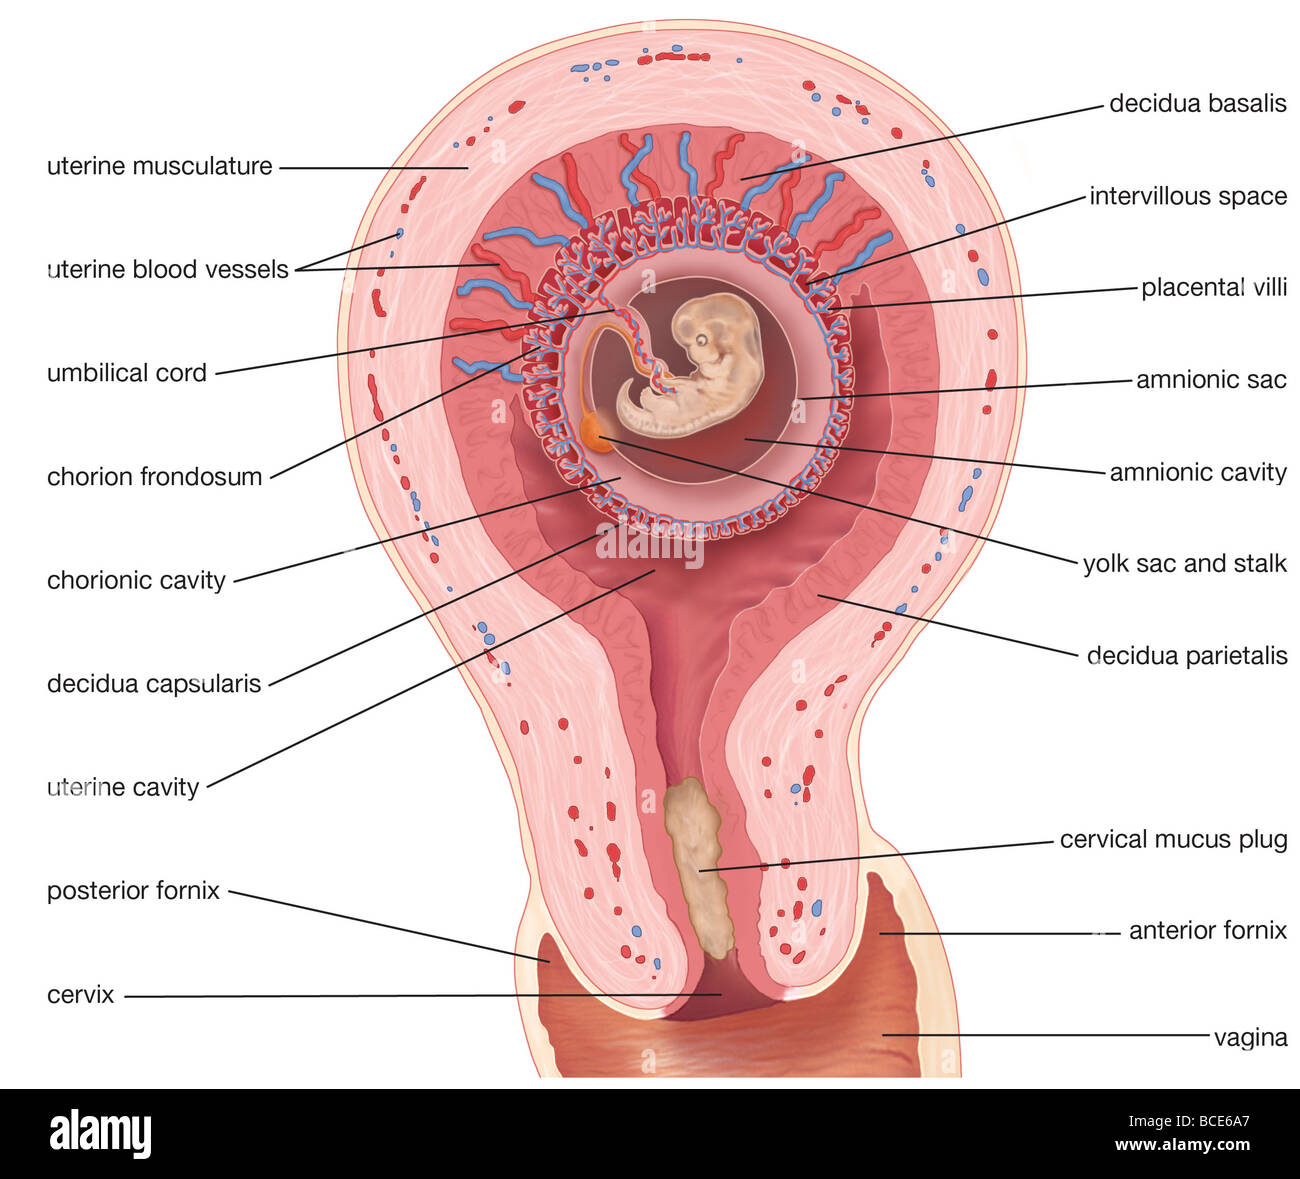

Amnionic Sac Hi res Stock Photography And Images Alamy